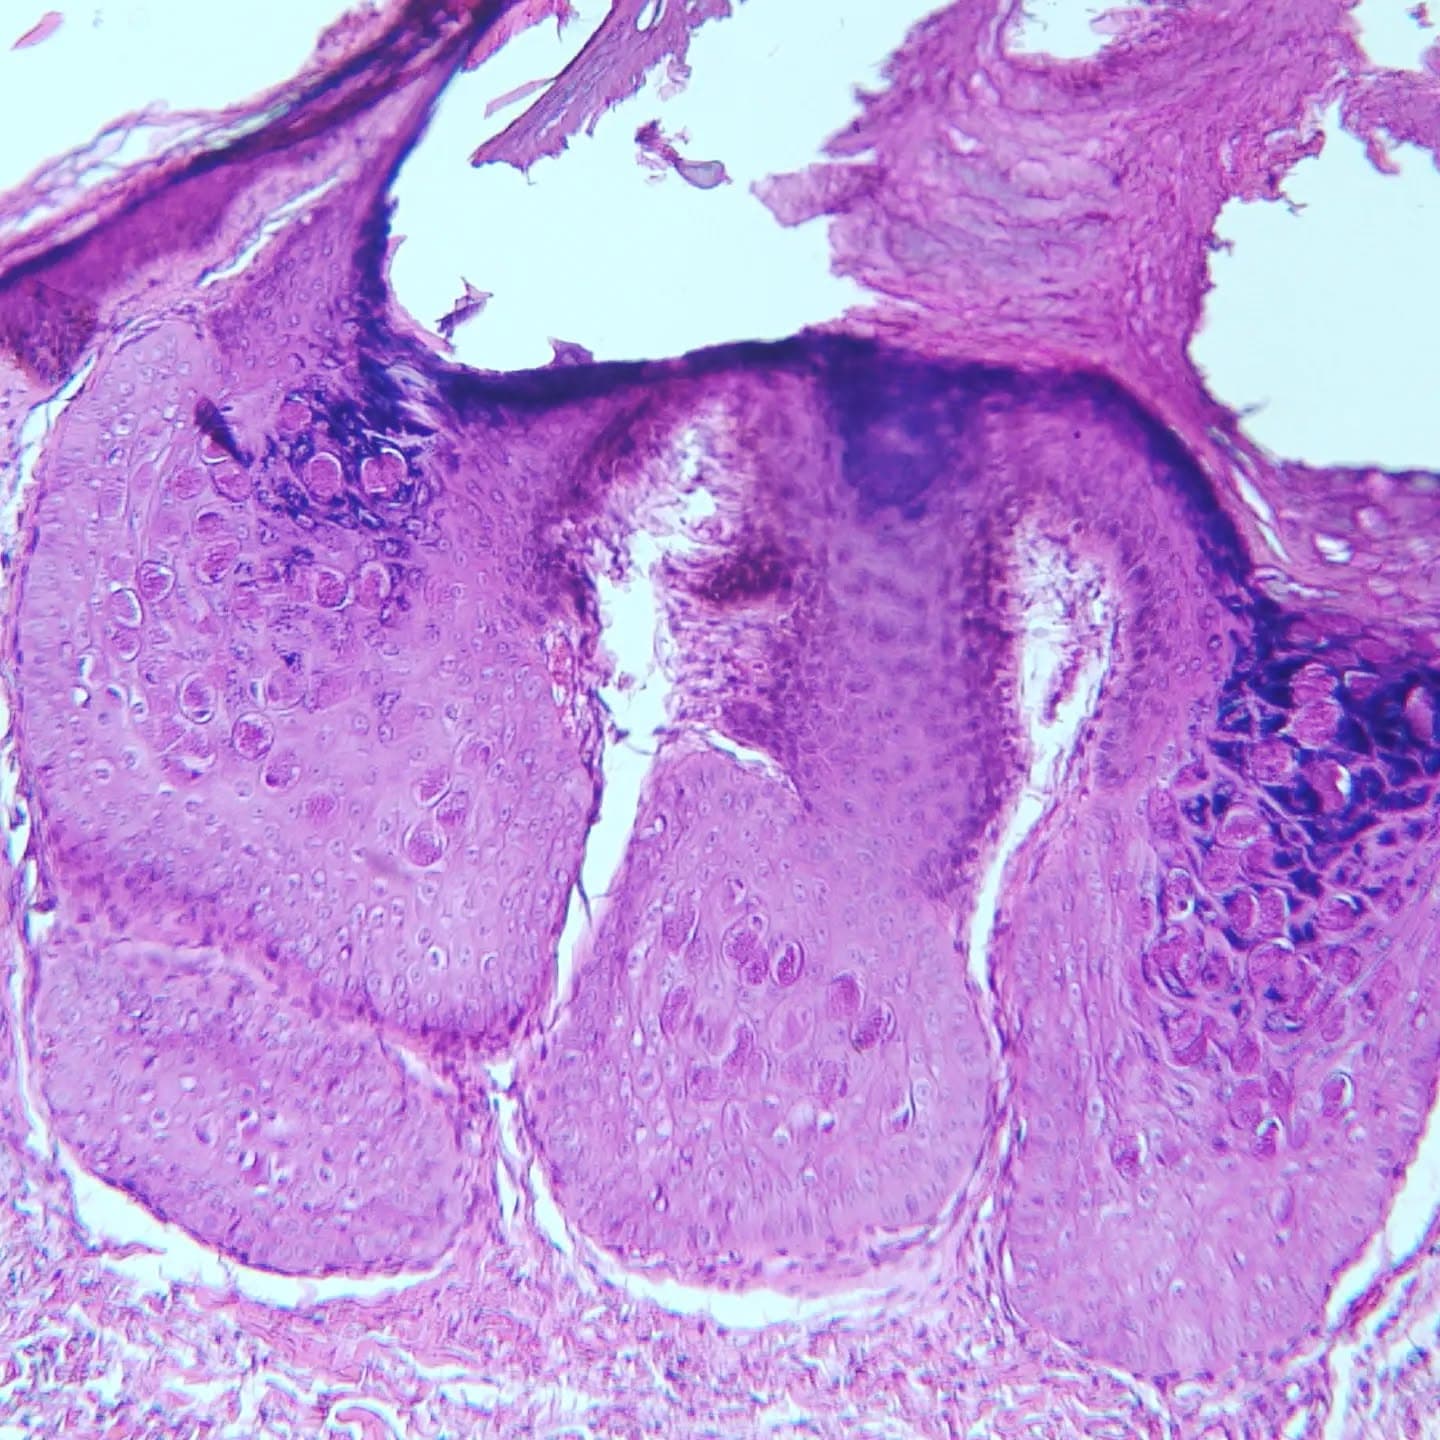

Caption: A 37 y/o female with thigh skin lesion. Dx: Molluscum contagiosum and intradermal melanocytic nevus! Located adjacent to each other